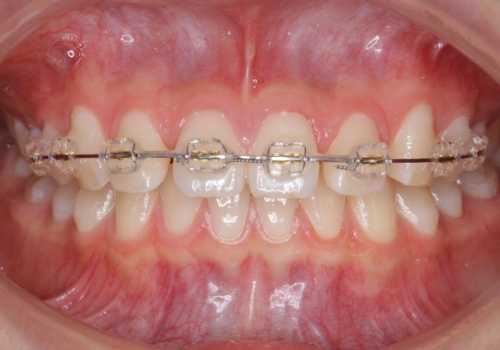

- 矯正装置

- ワイヤー矯正

- 治療期間

- 9ヶ月

- 前歯のすき間を気にして来院。

全体矯正ではなく部分矯正で治療することになりました。

その代わり、すき間をすべて閉じるのは難しく、両脇の目立たないところに集めて治療終了しています。